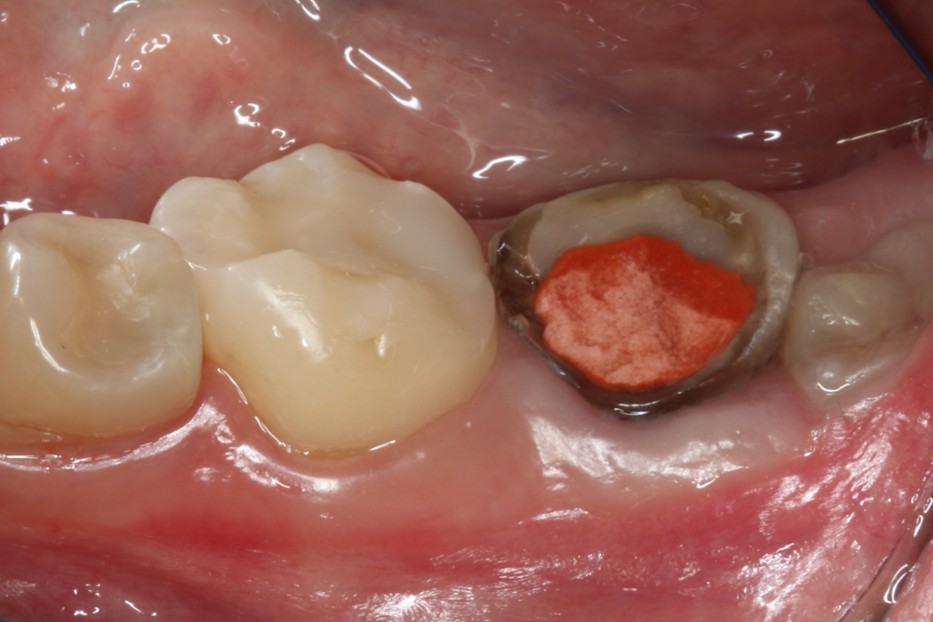

症例3

治療の流れ

親知らずの抜歯

| 患者様データ | 40代 女性 |

| 来院時の主訴 | 「左側奥歯で噛むと痛い。」 |

| 医院の診断 | 歯根破折、慢性根尖性歯周炎 |

| 通院期間 | 6か月 |

| 来院回数 | 9回 |

| 治療費 | 総額:330,000円(税抜) 【内訳】 歯牙移植150,000円、ファイバーポストコア20,000円、ダイレクトボンディング80,000円×2 |

| リスクと副作用 | ①根管治療歯は長期的には破折するリスク ②長期的なメインテナンスが必要 ③歯根の外部吸収 |

| ここがこだわりのポイント!☝ |

抜歯が必要になった際に余っている親知らずがあれば移植歯として利用することができます。 術前に撮影したCT画像から3Dプリンターを用いて親知らずのレプリカを作製することで、親知らずが乾燥することを防ぎ、成功率が上がるよう努力しています。 |